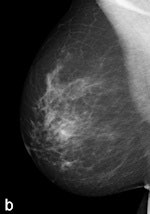

Another example of a finding in a left-sided craniocaudal view that was reported clearly more often by radiologists when using premium view (PV). A: Tissue equalization (TE) processed image. B: PV processed image with the annotation. C: Similar to image above, the resulting image of subtracting TE from PV. D: The thresholded version of C.For all six radiologists, perceived case suspiciousness -- defined as the highest probability of malignancy of all radiologist findings -- was higher using premium view optimization.

The major difference between the processing algorithms was an additional local contrast optimization when premium view was applied. "Premium view is aimed at increasing the visibility and suspiciousness of malignant lesions, but in our study the perceived suspiciousness of benign lesions and normal cases is increased as well," the researchers wrote. "An effect of local contrast enhancement could be that both normal (dense) structures and abnormal structures appear more suspicious due to their enhanced signal."

High-contrast images are usually preferred because of the increased visibility of the lesions, but the algorithm also affects normal cases. "In our study, the perceived suspiciousness of the normal cases increased even more than that of the malignant cases," they noted.